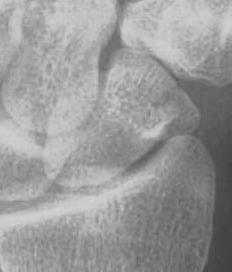

X-ray

5 images

- PA / lateral

- PA in 45° oblique pronation / PA 45o oblique supination

- PA in ulna deviation